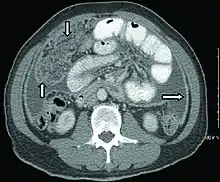

Extrapulmonary tuberculosis

Peritoneal tuberculosis may mimic peritoneal carcinomatosis on CT scan.[4]

There is low-quality evidence that abdominal ultrasound has 63% sensitivity and 68% specificity in diagnosing abdominal tuberculosis when tuberculosis is bacteriologically confirmed in HIV-positive individuals. Therefore, a negative abdominal ultrasound finding does not rule out the disease due to its low sensitivity.[5]